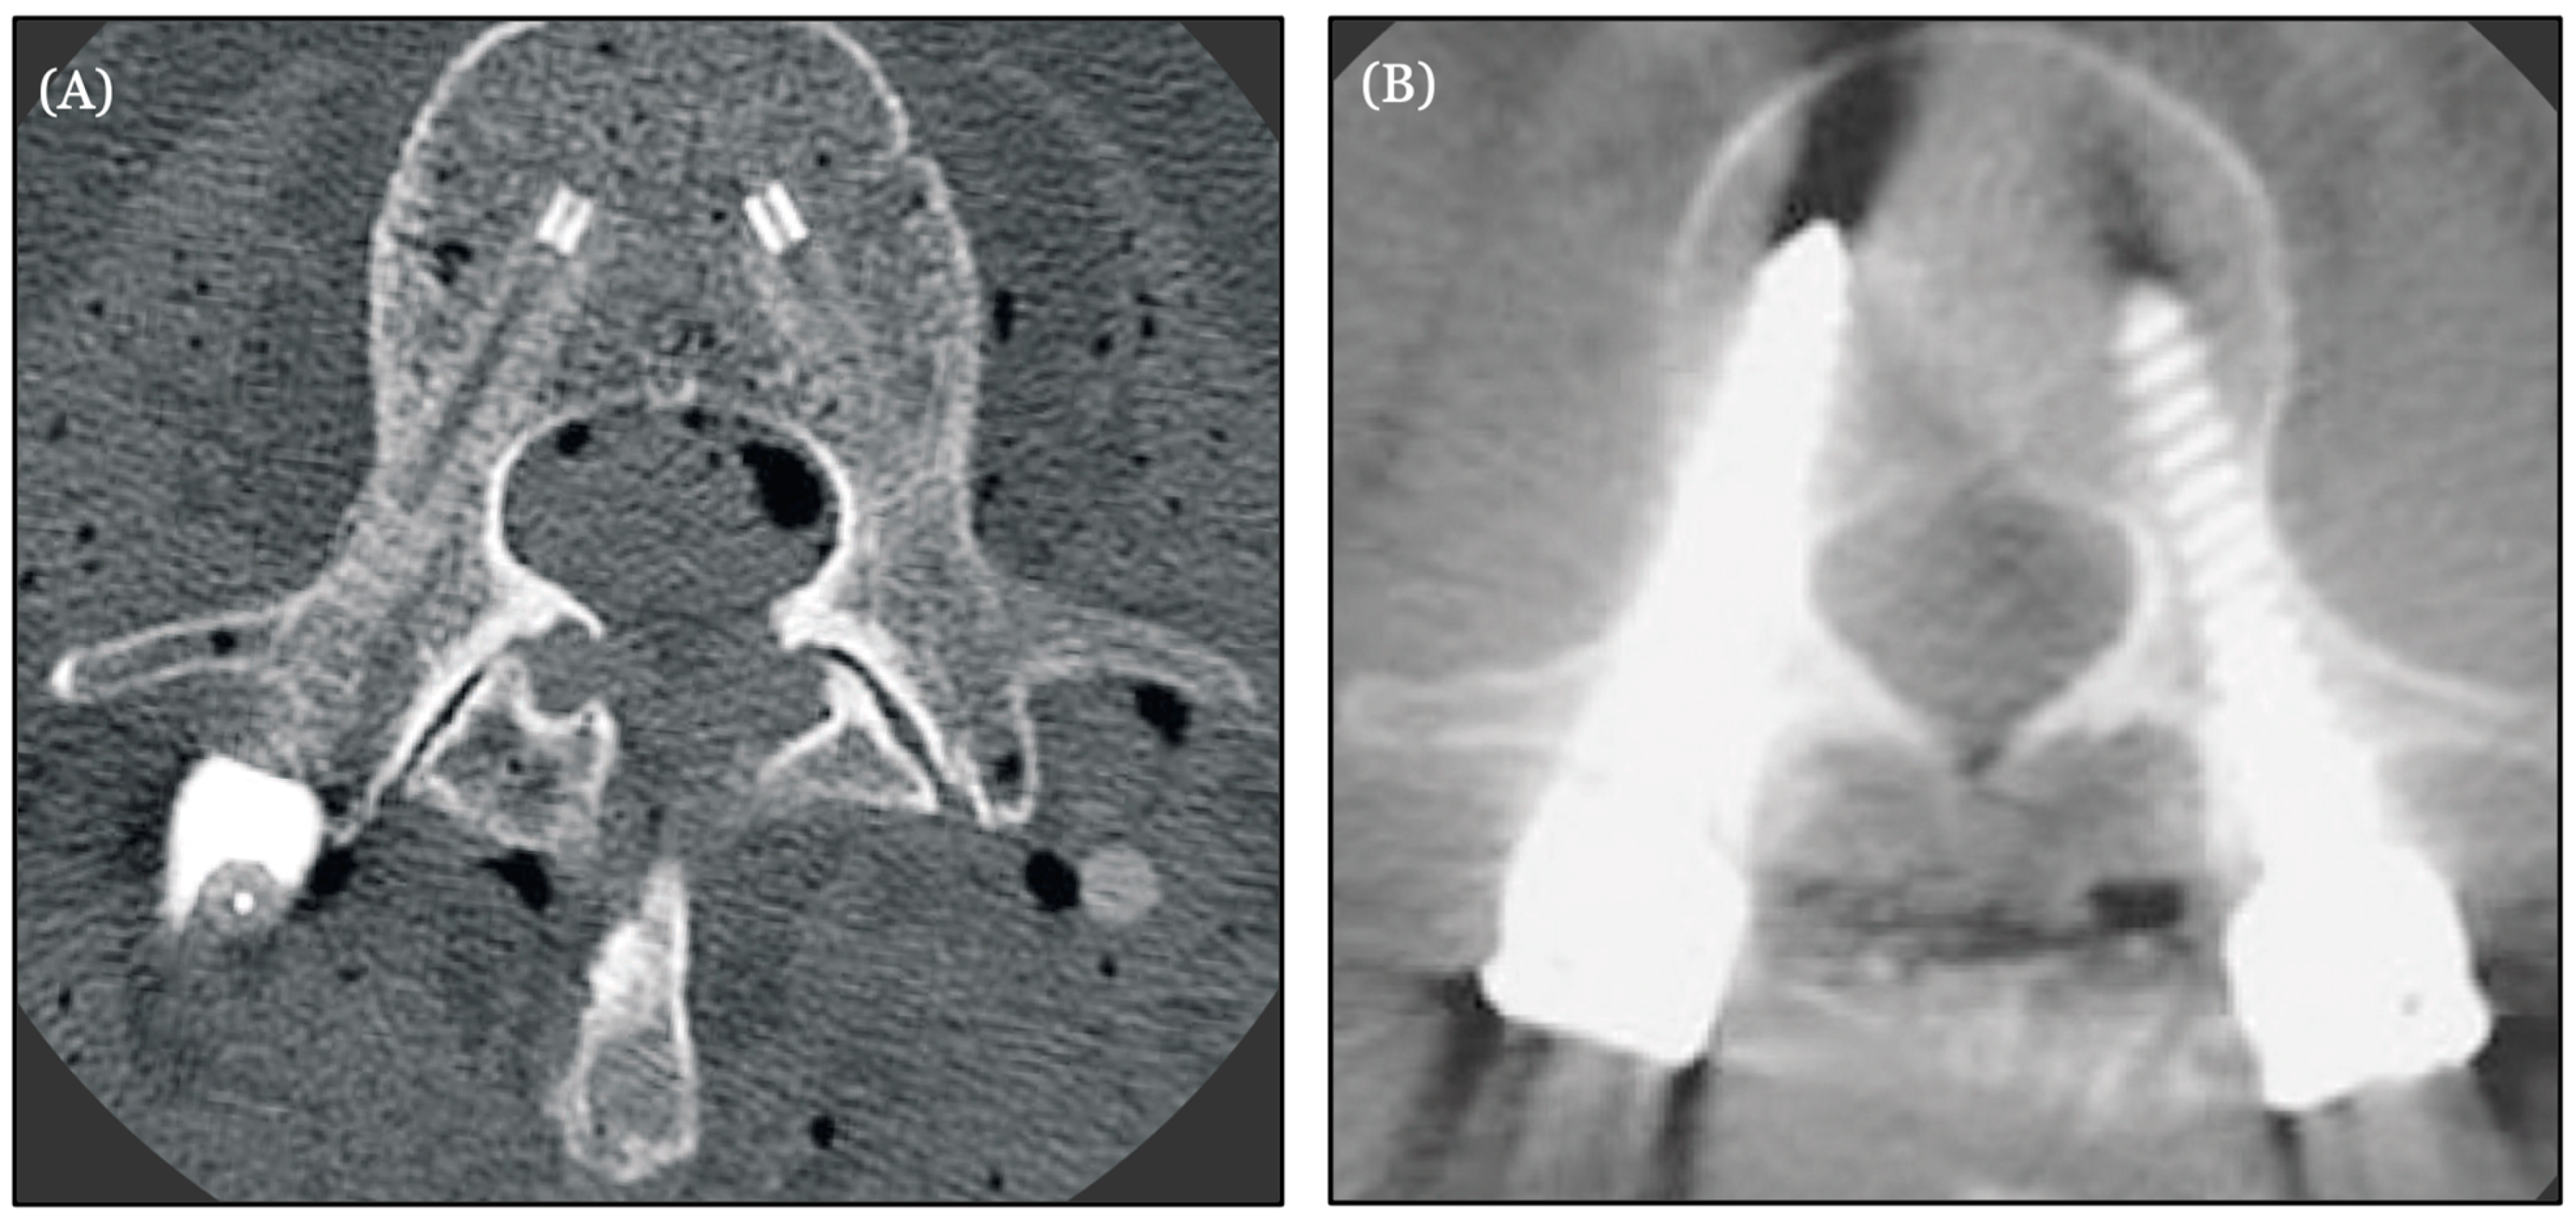

- Krätzig, T.; Mende, K.C.; Mohme, M.; Kniep, H.; Dreimann, M.; Stangenberg, M.; Westphal, M.; Gauer, T.; Eicker, S.O. Carbon fiber-reinforced PEEK versus titanium implants: An in vitro comparison of susceptibility artifacts in CT and MR imaging. Neurosurg. Rev. 2021, 44, 2163–2170. [Google Scholar] [CrossRef] [PubMed] [PubMed Central]

- Murthy, N.K.; Wolinsky, J.P. Utility of carbon fiber instrumentation in spinal oncology. Heliyon 2021, 7, e07766. [Google Scholar] [CrossRef] [PubMed] [PubMed Central]

- Hubertus, V.; Wessels, L.; Früh, A.; Tkatschenko, D.; Nulis, I.; Bohner, G.; Prinz, V.; Onken, J.; Czabanka, M.; Vajkoczy, P.; et al. Navigation accuracy and assessability of carbon fiber-reinforced PEEK instrumentation with multimodal intraoperative imaging in spinal oncology. Sci. Rep. 2022, 12, 15816. [Google Scholar] [CrossRef] [PubMed] [PubMed Central]

| Hubertus et al. (2022) | Carbon fiber reinforced PEEK (CFR-PEEK) | Evaluation of the performance and precision of 3D intraoperative imaging and navigation systems in thoraco-lumbar instrumentation with CFR-PEEK pedicle screws | Navigation accuracy was considerably lower for CFR-PEEK pedicle screws than reported for titanium implants. CT may be the best imaging modality for CFR-PEEK instrumentation assessment [55] | N |